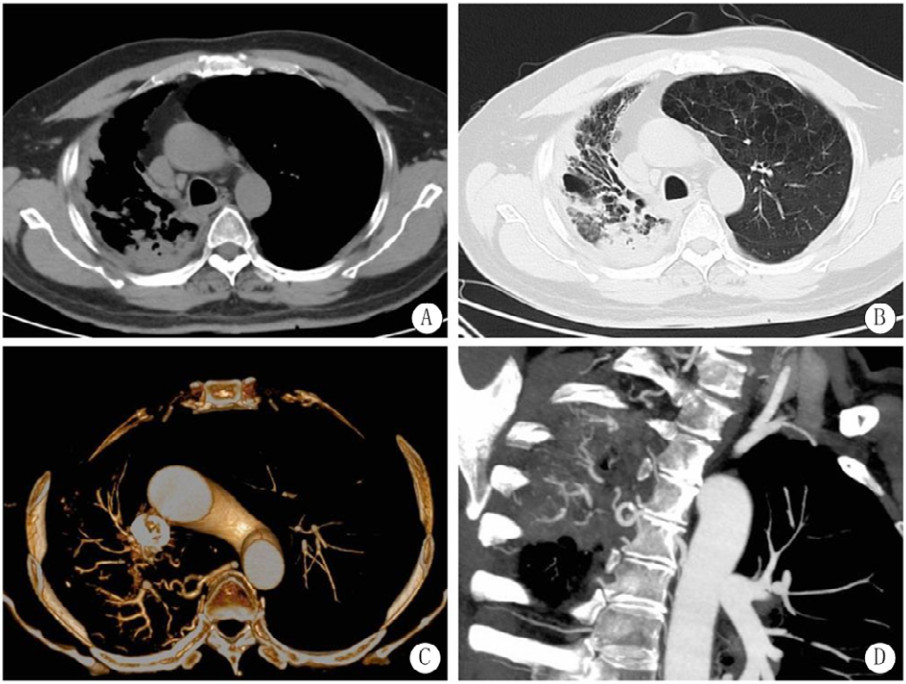

1 病例资料患者2019年7月开始出现发热、咳嗽、咳痰,外院胸部CT检查示两肺感染,予以抗感染治疗后症状稍好转。2019年12月,患者于江苏省中医院行气管镜检查,灌洗液中找到抗酸杆菌,肺穿刺示肉芽肿炎,抗酸染色呈阳性,诊断为肺结核并接受正规的抗结核治疗。后来在本院查胸部CT示右肺支气管扩张伴感染。治疗过程中,患者间断出现轻度咯血,给予止血等治疗后症状有所缓解。2023年3月患者再次出现咯血,咯血呈鲜红色,每日量20~200 mL不等。入住靖江市第二人民医院,给予止血和抗感染治疗,咯血仍间断存在,一周后转诊至本院进一步治疗。患者在病程中无畏寒发热、胸闷心悸、潮热盗汗等症状,入院查体:神志清楚,口唇无紫绀,颈静脉充盈正常,胸廓无畸形,呼吸节律正常,胸壁无静脉曲张,无结节和肿块,呼吸运动无减弱,肋间隙无增宽,语颤无减弱,触诊时无摩擦感,双肺叩诊呈清音,双肺呼吸音粗,右上肺可闻及湿性啰音,心率91次/min,心律规整,心音正常,双下肢无水肿。本院CT结果显示:右肺上叶陈旧性病变伴局部毁损、膨胀不全、支气管扩张、右侧胸膜增厚;断层摄影血管造影(computed tomography angiography, CTA)显示右支气管动脉增粗迂曲,远端分支增多杂乱(图 1)。入院诊断:支气管扩张伴咯血、陈旧性肺结核、2级高血压病(高危)。

| 注:A、B为CT示右肺上叶陈旧性病变伴局部毁损、膨胀不全、支气管扩张、右侧胸膜增厚;C、D为CTA示右支气管动脉增粗迂曲,远端分支增多杂乱,未见造影剂外溢 图 1 结核咯血患者CT及CTA表现 |